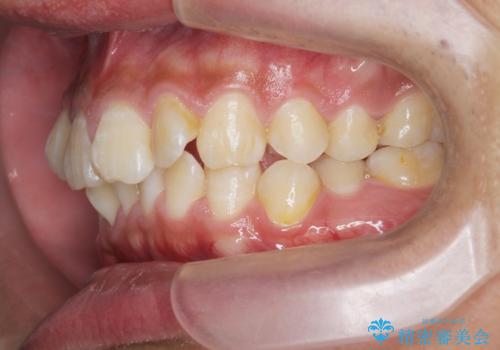

遠心移動を伴うマウスピース非抜歯矯正治療

- 「前歯の見た目を改善したい。」と矯正治療を希望され来院されました。

前歯のガタつきに加え、上顎が前にある咬合関係(上顎前突)を改善すべく、マイクロインプラントを用いた上顎奥歯の後方移動、拡大、ディスキングを用いたマウスピース矯正治療を計画します。